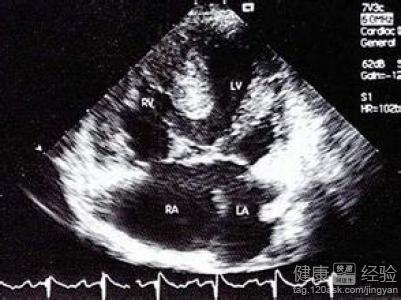

1該病也可以成為是心房內的一種缺損性的疾病,通常引起了該病症的發生,主要是由於患兒在胚胎期由於心室流入道的心內膜墊融合過程中的發育障礙所致。使患者的正常生活受到了不同程度的影響。

2而由於患者的發病症狀的不同和發育程度的差別,所以該病症是可以分為部分,過度甚至是完全型。而通常心房和心室水平的左向右分流使幾乎所有的心內膜墊缺損病人有大量肺血流。如果沒有室間隔缺損,血流動力學類似於大型房間隔缺損,右心室搏出量增加。